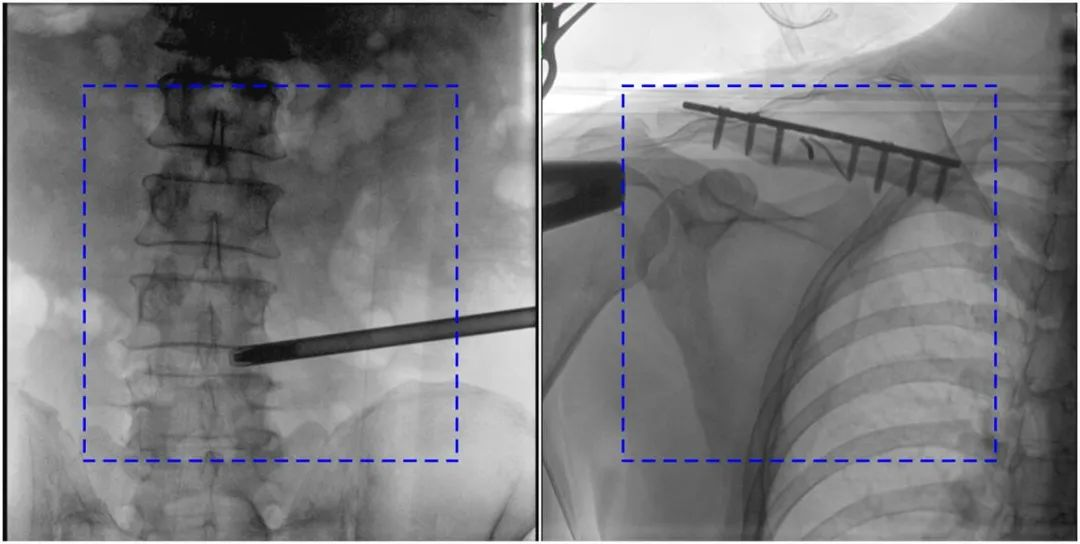

與傳統(tǒng)的21CM×21CM成像尺寸相比,普愛(ài)醫(yī)療大平板一體式C形臂具有30CM×30CM更大成像尺寸,能夠一次成像5.5節(jié)椎體,呈現(xiàn)更全面的影像信息,即便是手術(shù)經(jīng)驗(yàn)不豐富的年輕醫(yī)生也能通過(guò)圖像迅速判斷椎體節(jié)段、定位手術(shù)部位,避免因?yàn)橐曇安蛔愣斐傻亩啻味ㄎ?、反?fù)曝光,提高效率的同時(shí)避免過(guò)量攝入輻射。

普愛(ài)醫(yī)療大平板一體式C形臂圖像與傳統(tǒng)圖像對(duì)比(藍(lán)色虛線內(nèi)為傳統(tǒng)21CM×21CM平板的成像區(qū)域)